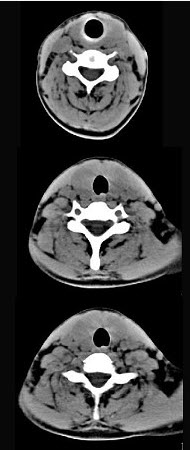

40岁,女性患者,双侧甲状腺肿大,CT扫描如图所示,请选择最佳答案()。

A:弥漫性甲状腺肿

B:甲状腺癌

C:甲状腺炎(桥本)

D:亚急性甲状腺炎

E:甲状腺瘤